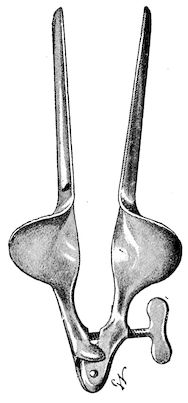

Fig. 1.—Rachitis in a young goat.